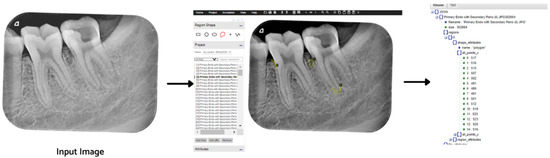

The ground truth of the obtained images was generated using a VGG Image Annotator (VIA) tool [21]. Five types of lesions were localized manually using bounding polygons around the carious regions. The annotations were saved in a JSON file, where each mask represents a set of polygon points. The pixels inside the bounding polygons corresponding to lesions were assigned values of 1 for primary endodontic, 2 for primary endo with secondary perio, 3 for primary periodontal, 4 for primary perio with secondary endo, and 5 for true combined, while the rest of the pixels were regarded as background with a value of 0. For each labeled data point, there is corresponding instance information as illustrated in Figure 3.

Figure 3.

Image labeling process using the VIA tool.